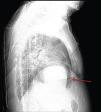

A 84-year-old woman was referred to our emergency department from another hospital with acute dyspnea at rest and hypoxemia. On admission a peripheral venous catheter had been inserted for fluid replacement and she had undergone computed tomography pulmonary angiography (CTPA) for suspected pulmonary embolism. Soon after the exam the patient became confused and drowsy and her respiratory failure worsened significantly without hemodynamic instability. CTPA confirmed the presence of bilateral central and peripheral thrombus and a large amount of air in the brachiocephalic veins, pulmonary artery (Figure 1) and right ventricle (Figures 2 and 3). She was considered to have VAE unrelated to the administration of contrast, given a topogram image that suggested the presence of air in the right ventricle before contrast injection (Figure 4). It was therefore assumed that the VAE resulted from the placement or manipulation of the peripheral venous catheter previously inserted in another institution. The patient was immediately given normal saline, a Hudson mask was applied and she was placed in left lateral decubitus position (Durant's maneuver) and in the Trendelenburg position, to keep the right ventricular outflow tract lower than the right ventricular cavity causing the air to migrate upwards, minimizing the likelihood of embolism. Her clinical status improved rapidly and she recovered without sequelae. Bedside transthoracic echocardiography showed no acute ventricular dilation or dysfunction, and the patient was transferred to another hospital for hyperbaric oxygen therapy.